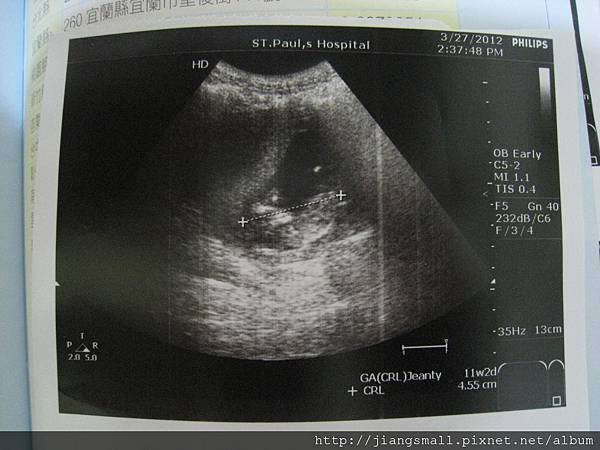

3/27

第一次產檢

照超音波的時候,看到BB腳腳在踢來踢去….哈….上次手舉起來….。

身高: 4.5cm。正常。

預產期: 10月17日。